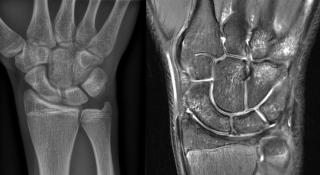

Op onderstaande figuur is zichtbaar hoe de radiografie (links) geen fracturen toont. De coronale T2-gewogen opname met vetonderdrukking toont daarentegen meerdere zones van beenmergoedeem, passend bij spongiosafracturen in de carpalen en metacarpalen. Deze MRI-bevindingen verklaren de aanhoudende last ondanks een normale radiografie.

MRI met meerdere zones van beenmergoedeem, passend bij spongiosafracturen in de carpalen en metacarpalen